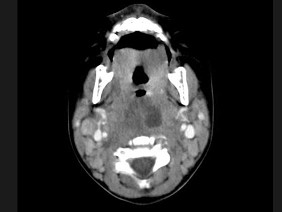

18.10个月大的婴儿,发热,曾患中耳炎,CT扫描如图所示,请选择正确的描述或诊断 ( )![]() ![]() ![]() |

| 正确答案:ABCD |